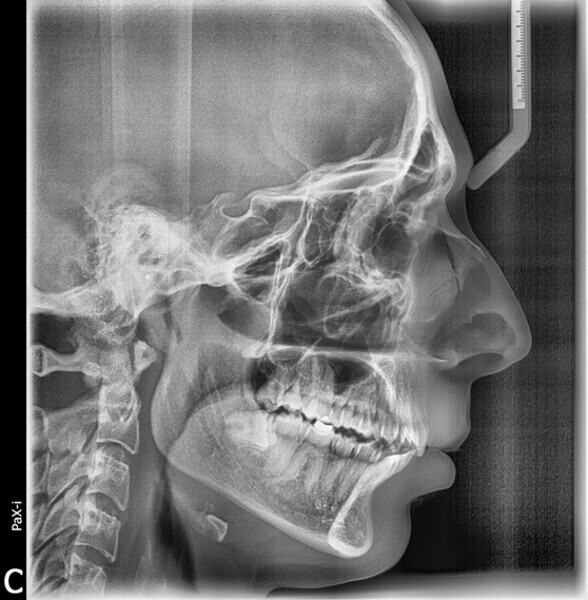

Four years after this case had been completed, the patient came for a review, and both radiographic and photographic records were taken to evaluate any changes that may have occurred over this retention period (Figs. 26–30). Cephalometric analysis was performed again and the results compared with the immediate post-treatment results (Table 2).

The radiographic equipment used on this occasion was not the same as we had used before, so the results obtained should not be considered totally accurate. Despite this setback, the patient’s status remained significantly better than at the beginning of treatment, since the patient still had a Class I occlusion, his profile was harmonious, and most notably, he was still satisfied with the results.